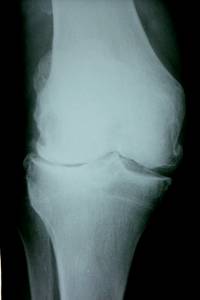

Der zunehmende Verschleiß der großen, aber auch der kleinen Gelenke des menschlichen Körpers führt immer wieder zu teilweise sehr belastenden Schmerzen.

Doch nicht nur der Schmerz sondern auch die schrittweise Abnahme der Mobilität durch Bewegungseinschränkungen der betroffenen Gelenke sind für eine zunehmende Minderung der Lebensqualität verantwortlich.